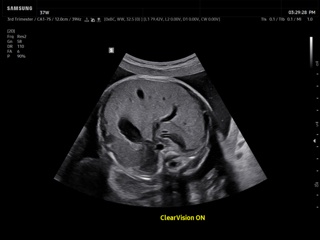

Atlas of ultrasound images - obsterics

In the section "Оbsterics" of atlas the results of ultrasonic examinations of pregnant women with different durations of gestation are represented. Here you can see images of internally organs, cerebrum, cordis and the sex of the fetus, the sonograms of multiple pregnancy, the blood flow in placenta and umbilical cord, defects of fetal`s development, etc.